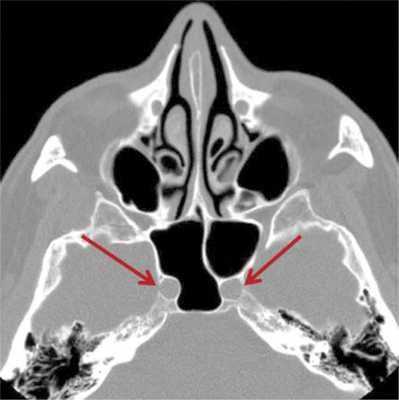

Прободение удобнее производить острой ложкой, загнутая рабочая часть которой поможет избежать ранения внутренней сонной артерии. Место вскрытия клиновидной пазухи — нижнемедиальный отдел задней клетки решетчатого лабиринта: сразу за костной перемычкой книзу от канала зрительного нерва часто расположен канал внутренней сонной артерии (ее наиболее выступающий в клиновидную пазуху отдел — сифон, или переднее колено). Костные перемычки между клиновидными пазухами, а также между сфеноэтмоидальной клеткой и клиновидной пазухой нередко указывают (рис. 2, 3) Рис. 2. На аксиальной томограмме околоносовых пазух каналы внутренних сонных артерий указаны красными стрелками. на присутствие канала внутренней сонной артерии [1].